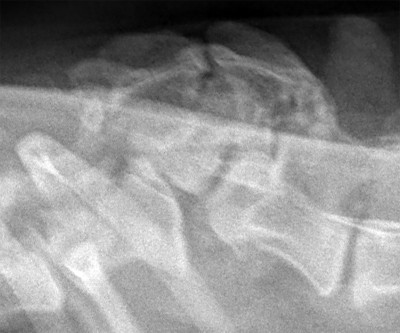

Wir waren mit Moses zur Kontrolle in der Tierklinik

Die "Bruch-"Stelle ist noch weiterzusammengewchsen, so dass der TA meinte, dass "wenn an Moses Rücken noch einmal etwas passieren würde, es an einer anderen Stelle sein würde, weil die Verletzungsstelle inzwischen äußerst stabil ist."

Das ist die vordere hochstehende Stelle, die hintere ist der Beckenknochen.